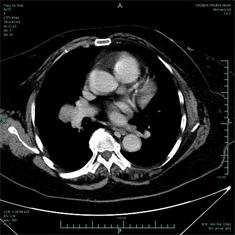

近日我科收治了3例在多家医院无法确诊的疑难病例,均在接诊后第一时间通过介入或者影像技术确诊。上月初我科收治一右侧肺门肿大的患者,该患者既往有淋巴瘤病史,曾在我市多家医院就诊,无法探明肿块具体病因,后转至上海某著名医院,对肿块进行了经皮肺穿刺活检,但仍然无法确诊,后求诊我院,我科俞万钧书记,彭卫东主任等在接诊后第一时间对其进行支气管镜检查,同时凭临床经验行TBLB,对肿块进行定位活检,1周后患者病理证实鳞癌。上月中旬,又一患者慕名来至我科,要求确诊病因。该患者为一老年男性,左侧肺部靠近肺动脉处发现2个结节,我市多家市级医院通过支气管镜等手段无法确诊,后转至上海某著名专科医院,仍然无法确诊,后经人介绍,至我科,我科俞万钧书记,彭卫东主任等制定经皮穿刺方案,因病灶靠近肺动脉,我科在CT室李胜主任的协助下,凭借丰富临床经验取得活检标本,证实肿块为结核,患者感激涕零。本月初,一中年男性因发热1月余,来我院就诊,在我院就诊前,该患者先后就诊于我市多家县市医院,后转至杭州专科医院,均无法确诊,患者万般无奈,承受着肉体和精神的煎熬,来我科就诊。第二天,查房,我科俞万钧书记,彭卫东主任,徐涛副主任医师等通过读片,重点怀疑是患者的腹部炎症感染,通过CT室李建斌医师的帮助,对患者的病灶进行三维重建,确诊患者为膈下慢性脓肿,DSA马霁波医师进行穿刺,引流出脓液将近1000ml,患者体温渐渐恢复正常,目前患者康复中。我科近年来,特别是去年以来,在俞万钧书记的带领下,呼吸介入水平突飞猛进,同时积极寻求多科合作,和我院肿瘤放化疗科,影像科,CT室,病理科等保持密切合作,共进互助,努力为患者解除病魔痛苦,更好地为人民健康服务。(徐涛)